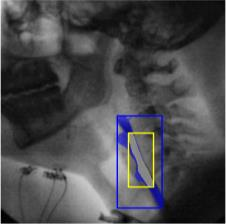

The videofluoroscopic swallowing study (VFSS) is a gold-standard imaging technique for assessing swallowing, but analysis and rating of VFSS recordings is time consuming and requires specialized training and expertise. Researchers have recently demonstrated that it is possible to automatically detect the pharyngeal phase of swallowing and to localize the bolus in VFSS recordings via computer vision, fostering the development of novel techniques for automatic VFSS analysis. However, training of algorithms to perform these tasks requires large amounts of annotated data that are seldom available. We demonstrate that the challenges of pharyngeal phase detection and bolus localization can be solved together using a single approach. We propose a deep-learning framework that jointly tackles pharyngeal phase detection and bolus localization in a weakly-supervised manner, requiring only the initial and final frames of the pharyngeal phase as ground truth annotations for the training. Our approach stems from the observation that bolus presence in the pharynx is the most prominent visual feature upon which to infer whether individual VFSS frames belong to the pharyngeal phase. We conducted extensive experiments with multiple convolutional neural networks (CNNs) on a dataset of 1245 bolus-level clips from 59 healthy subjects. We demonstrated that the pharyngeal phase can be detected with an F1-score higher than 0.9. Moreover, by processing the class activation maps of the CNNs, we were able to localize the bolus with promising results, obtaining correlations with ground truth trajectories higher than 0.9, without any manual annotations of bolus location used for training purposes. Once validated on a larger sample of participants with swallowing disorders, our framework will pave the way for the development of intelligent tools for VFSS analysis to support clinicians in swallowing assessment.